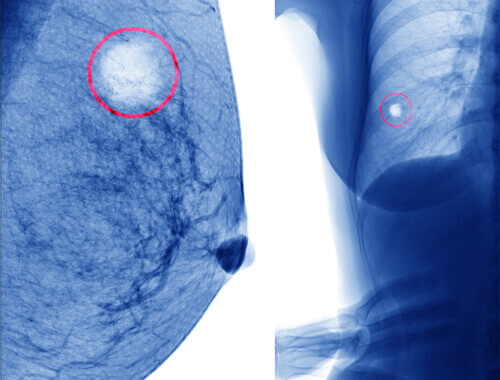

Borstkanker krijgen is een van de grootste angsten van veel vrouwen. Een knobbeltje in je borst is echter niet per se een teken dat je borstkanker hebt. In dit artikel gaan we in op enkele van de verschillende soorten cysten die er bestaan, en wat je moet doen als een zelfonderzoek of een medisch onderzoek van je arts gezwellen of cysten aan het licht brengt.

Een borstcyste is een verzameling vloeistof aan de binnenkant van de borst. Het is dus een klein zakje, meestal ongeveer zo groot als een kikkererwt of kleiner, dat meestal vloeistof bevat.

Als je tijdens je routine borstonderzoek een of ander knobbeltje vindt, is het raadzaam naar de dokter te gaan om een eenvoudige biopsie te laten doen. Als het vloeibaar of halfvast is en er geen andere tekenen zijn, zoals bloed, die op negatieve bijwerkingen wijzen, is het in 98% van de gevallen gewoon een eenvoudige cyste.